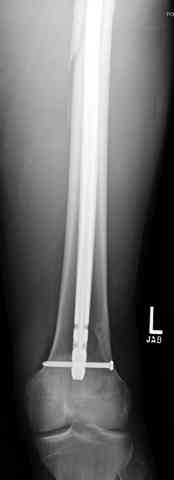

Здесь представлены несколько случаев лечения огнестрельного перелома

1 Проксимальный перелом бедра, антеградный гвоздь

2 внутрисуставной перелом дистального бедра с удалением пули

3 сегментарный перелом бедра с переломом Хоффа фрагментом, сделано из минимального доступа